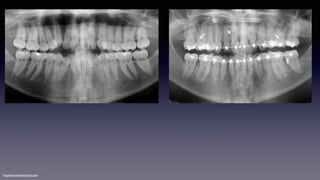

•Class II div 2

MaHe220611